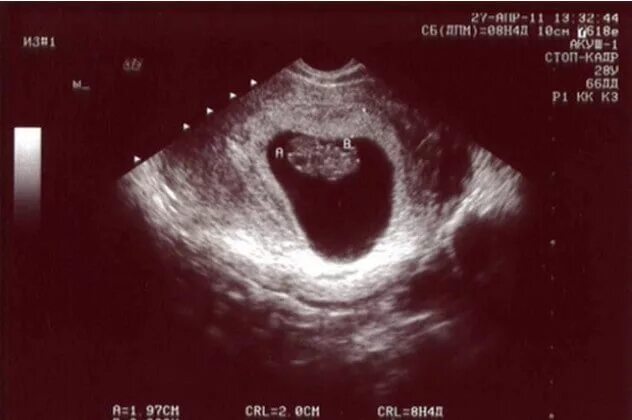

Плод на 9 неделе беременности